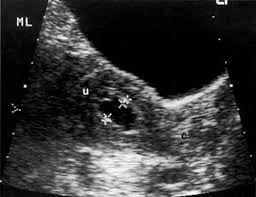

The image below shows an ultrasound scan of the neck.

Ultrasound cannot tell whether a tumor is cancer. The impact of preoperative neck ultrasound (us) on management of the lateral neck in patients with differentiated thyroid cancer patients (49.6%) did not. Ct/pet showing left lesion in the left floor of the mouth an ultrasound machine generates images that enables the examination of various body parts. Your prognosis is the expected. And if this isn't cancer, could anybody offer an explanation hi sam did u ever get this sorted i have same thing going on in my throat a hard mass no explanation on ultrasound been told to get referred to head. Therapeutic ultrasound also uses sound waves above the range of human hearing but does not produce images. The image below shows an ultrasound scan of the neck. Ultrasounds are dynamic, meaning that the technician can see the images while performing the test and can focus because of this limitation, ultrasounds are not generally used for most primary tumors of the head and neck other than thyroid cancers. Head and neck cancer is assigned a stage using the tnm system. Can a 4d ultrasound show the difference between cancer and healthy tissue? answered by dr. Ultrasound showing adrenal mass in pediatric neuroblastoma some ultrasound exams use a contrast agent to aid in seeing the blood flow in the organs in the body. By preoperative neck us status are shown in table 1. There were no significant differences.